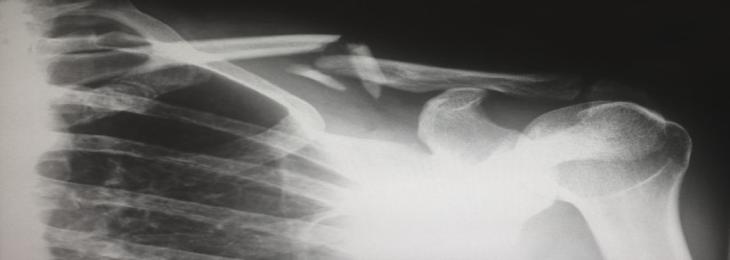

Scientists used sound waves to transform stem cells into bone cells, in a tissue engineering development that one day could help patients regenerate bones lost to diseases such as cancer

Many cancer patients or people suffering from degenerative diseases lose bones due to the disease. Replacing or regrowth of these bones could be a complex and often painful procedure. Now researchers at RMIT developed a new way to turn stem cells into bone cells rapidly and efficiently with the use of high-frequency sound waves.